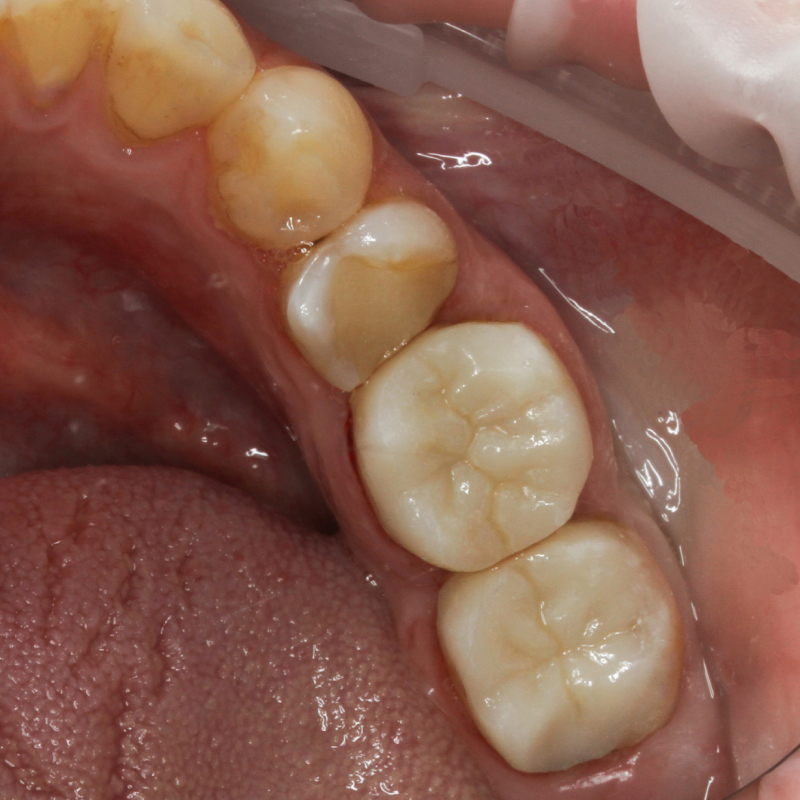

До и после лечения

Пациент обратился в «Стоматологию Комфорта» с жалобами на разрушенное состояние зубов, невозможность полноценно пережевывать пищу. В ходе диагностики врач Шандро Евгения Богдановна поставила диагноз: кариес дентина зубов 3.6, 3.7. Врач принял решение о лечении кариеса с заменой непригодных композитных реставраций на керамические накладки Оверлей.

Керамическая накладка Overlay полностью перекрывает щёчную и нёбную поверхности зуба. Конструкция обеспечивает идеальное смыкание с тканями ротовой полости, повторяет индивидуальные особенности рельефа естественных зубов. Накладка практически не даёт усадку, препятствуя повторному образованию кариеса. Материал накладки не темнеет и не окисляется.